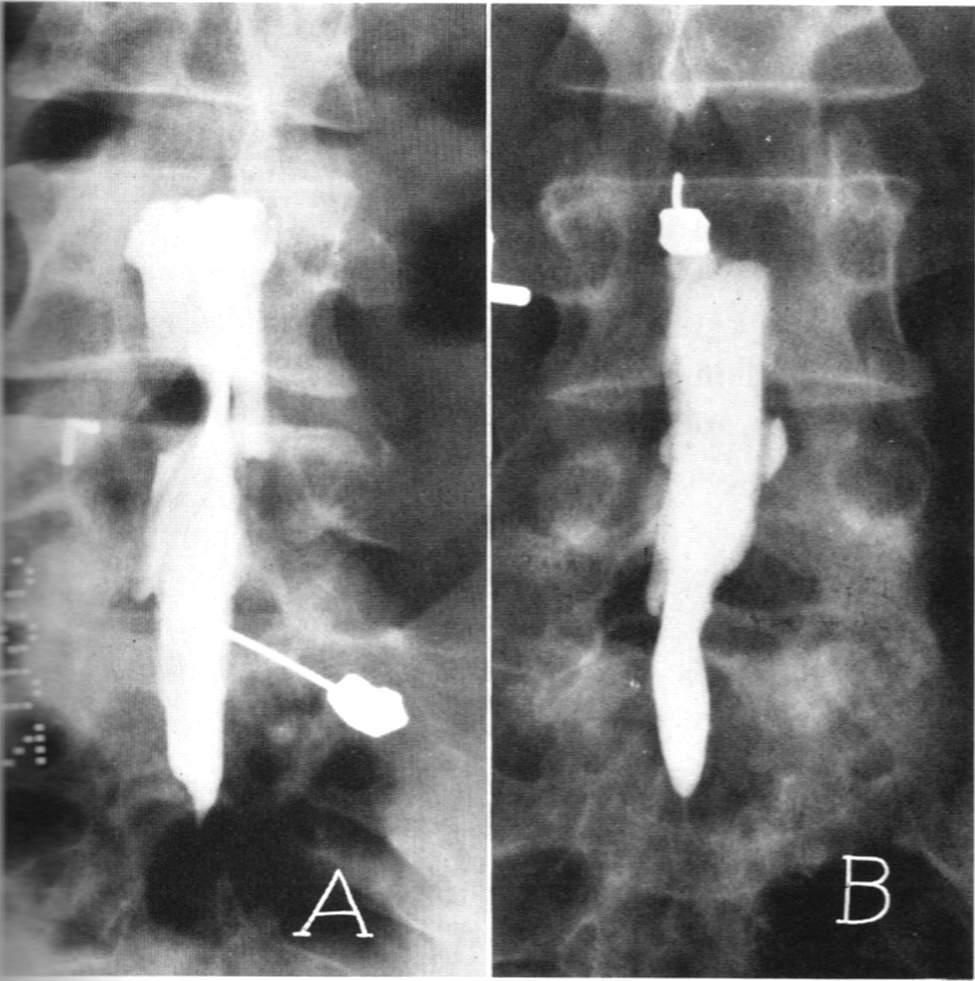

脊髓造影:往脊髓腔里面打造影剂后拍个片子,准确率可以达到80%,但无法良好的显示神经根,同时有创,一般很少用。

磁共振检查:跟CT一样,具有确诊价值,同时由于其成像原理,对于观察神经以及是否存在神经压迫水肿信号,有独特的优势,也是目前诊断腰椎间盘突出,明确神经压迫的主要检查,老百姓没学过医的也可以看得到的“突出”!